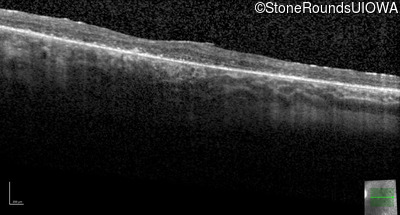

Optical Coherence Tomography - Left - 20/50

Exemplar / OCT Stack